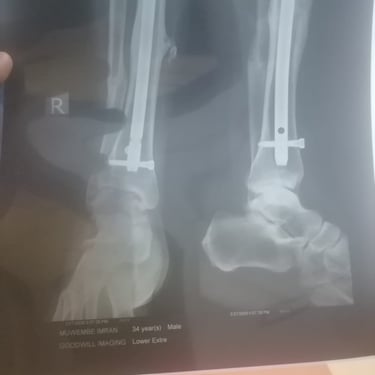

Imran Muwembe, founder of Rakai Vulnerable Home Center in Uganda, needs emergency surgery.

Years ago, while working in South Africa, he was hit by a car. His leg was saved with steel plates. After receiving a modest victim’s settlement, he returned to Uganda and used the money to start a home for orphaned children instead of rebuilding his own life.

Doctors advised that the plates be removed after four years, but he could not afford the procedure.

Now he is in extreme pain — with severe leg swelling, sacral nerve complications, and constant fever. Specialists warn the damage could become permanent without urgent treatment.

He needs $900 to cover surgery and essential hospital costs.